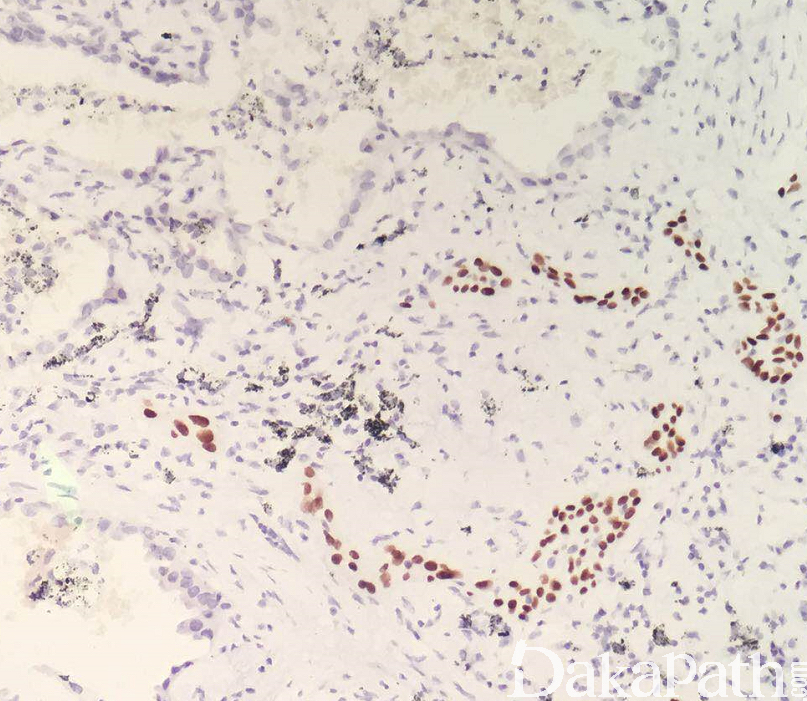

免疫组织化学染色:

鳞状细胞癌成分 p63. p40. CK5/6 阳性,腺癌成分 Napsin A、TTF1. CK7 等常阳性,对于分化差的,单纯形态学诊断有困难的病例可免疫组织化学染色辅助诊断。